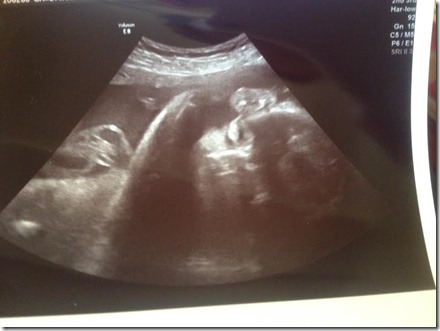

On Monday I had another appointment, and even an ultrasound. The tech was really great and spent a lot of time with me pointing things out, and just letting me see baby girl move around. She had her hands up by her face, feet up by her head, and was sticking her tongue out. I feel so much better after seeing her again and knowing she’s still ok.

Interesting development, baby M is measuring ahead! Like, almost two weeks ahead! The day of the appointment I was 27 weeks 6 days, and I am measuring 29 weeks four days. No wonder I feel so big! I wasn’t a big baby and neither was Bobby, so we will see what happens as we get closer.